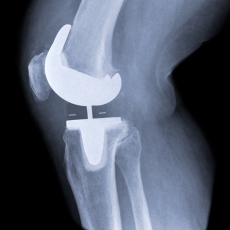

During the surgery, a surgeon removes damaged cartilage and some bone from the surfaces of your knee joint. Cartilage is tissue that covers your bones where they meet. Healthy cartilage is smooth and helps the bones glide over each other when you move. When cartilage becomes rough and wears away, the bones rub against each other, causing pain.

After removing the damaged knee cartilage and bone, the surgeon attaches the artificial parts to your bones. The artificial parts are made of metal and plastic. They will give your knee new, smooth surfaces.

Knee replacement surgery may replace all the damaged parts of your knee (total knee replacement) or just part of your knee (partial knee replacement). In a total knee replacement, the surgeon replaces 3 surfaces:

- The end of the shinbone

- The end of the thighbone

- The back of the kneecap